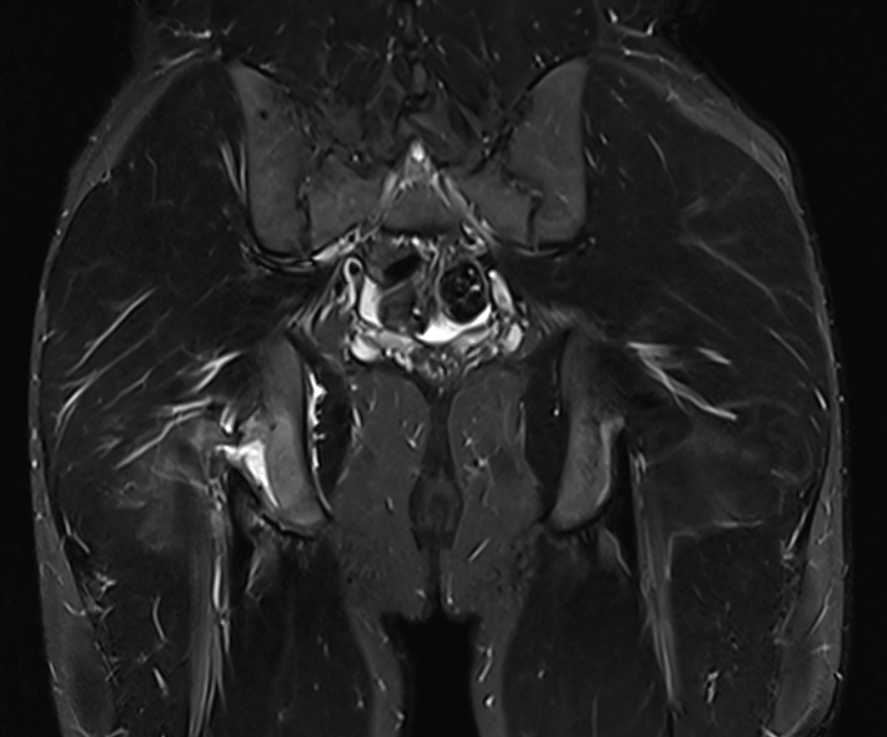

3. Right common hamstring tendon apophyseal avulsion